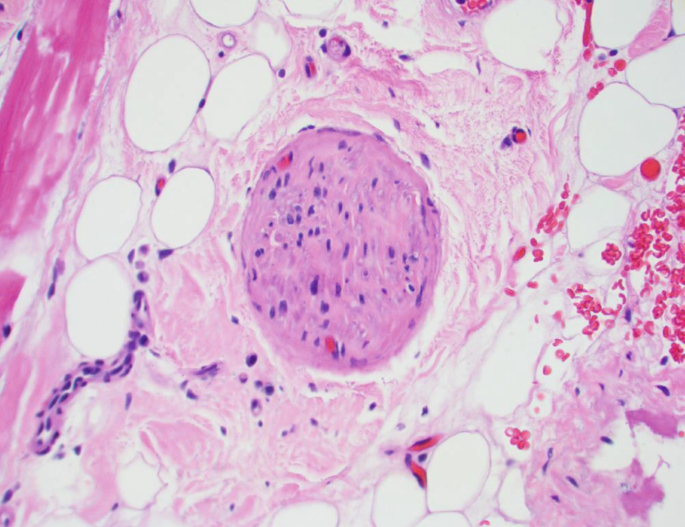

The composition of the epidermis dermis and subcutaneous fat is reviewed in great detail. This chapter discusses the structure histology and function of the skin. Practice all cards Apocrine glands Coiled structures attached to hair follicles found in.